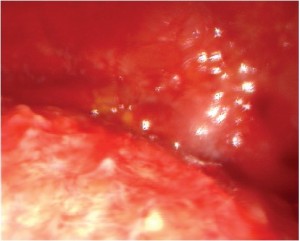

This is a 79-year old man with previous occupational asbestos exposure presenting with unilateral left-sided pleural effusion. Initial CT-scan showed a thickened pleura within the left chest (Figure 1). After video-assisted thoracoscopic exploration, MPM was provisionally diagnosed on the basis of macroscopic intraoperative view (Figure S1). Pleural biopsy confirmed the diagnosis of epitheloid MPM. The patient underwent RP with resection and reconstruction of the diaphragm due to local infiltration (Video 1). Adequate MCR was achieved at the end of surgery. The patient was extubated immediately after surgery and transferred to the intensive care unit. The postoperative X-ray of the chest showed a fully expanded lung on the left side. The final examination of the resected specimens confirmed the pathological IMIG stage III [pT3 N0 (0/23)].